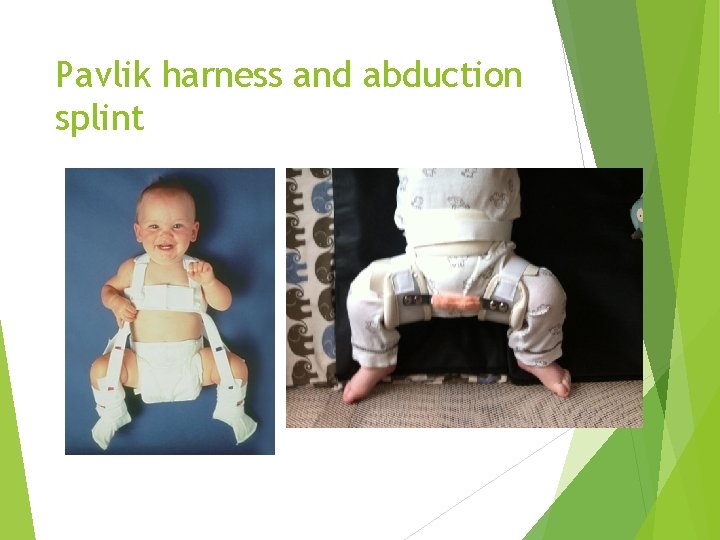

Pavlik harness or abduction splint Pavlic Harness is dynamic brace that maintains the hip in flexion and abduction, less stiffness , enhance deepening of acetabulum, and less AVN more time to apply and needs co-operative parents Abduction splint: static splint that maintains the hip in flexion and abduction , no movement so more stiffness, less deepening of acetabulum and more AVN easy to apply

Pavlik harness and abduction splint